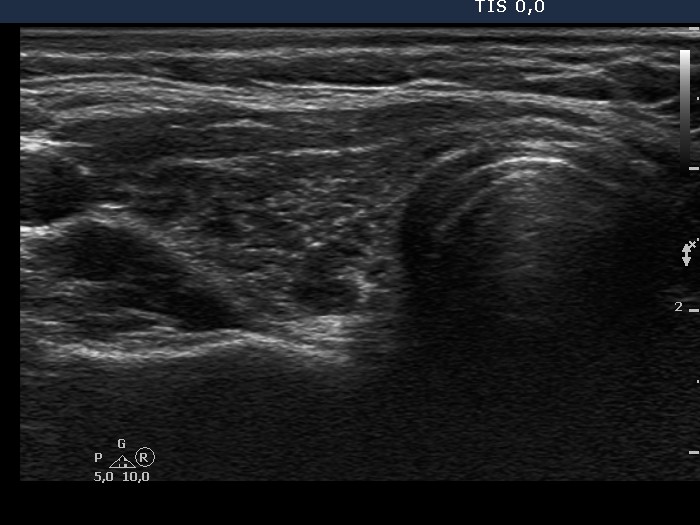

Chronic lymphocytic thyroiditis - Case 36. |

Clinical data: a 35-year-old woman with hypothyroidism replaced with 100 ug levo-tiroxin was referred for evaluation of thyroid nodules.

Ultrasonography: there were several circumscribed areas which in fact did not fit nodules. These are active foci of autoimmune thyroiditis.

Cytological report: benign Hashimoto's thyroiditis.